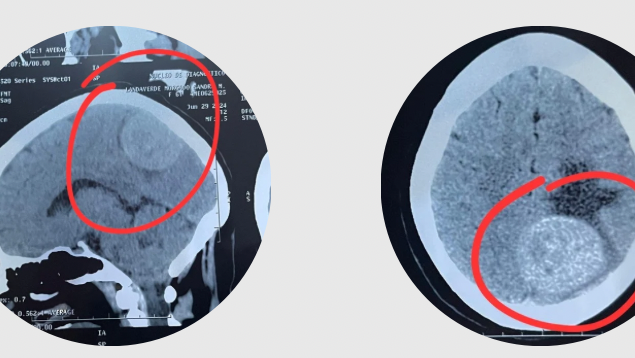

¡Hola! A mi mamá Sandra Landaverde Morgado le detectaron un tumor en el cráneo llamado meningioma y es necesario hacerle una operación ya que los daños que cause podrían ser irreversibles, por lo que estamos realizando una recaudación de fondos para que se pueda operar lo más pronto posible.

El tumor está afectando los sentidos del habla, de la vista y le ocasiona convulsiones e incluso puede ocasionar problemas respiratorios ya que se encuentra cerca de la base del cerebro.